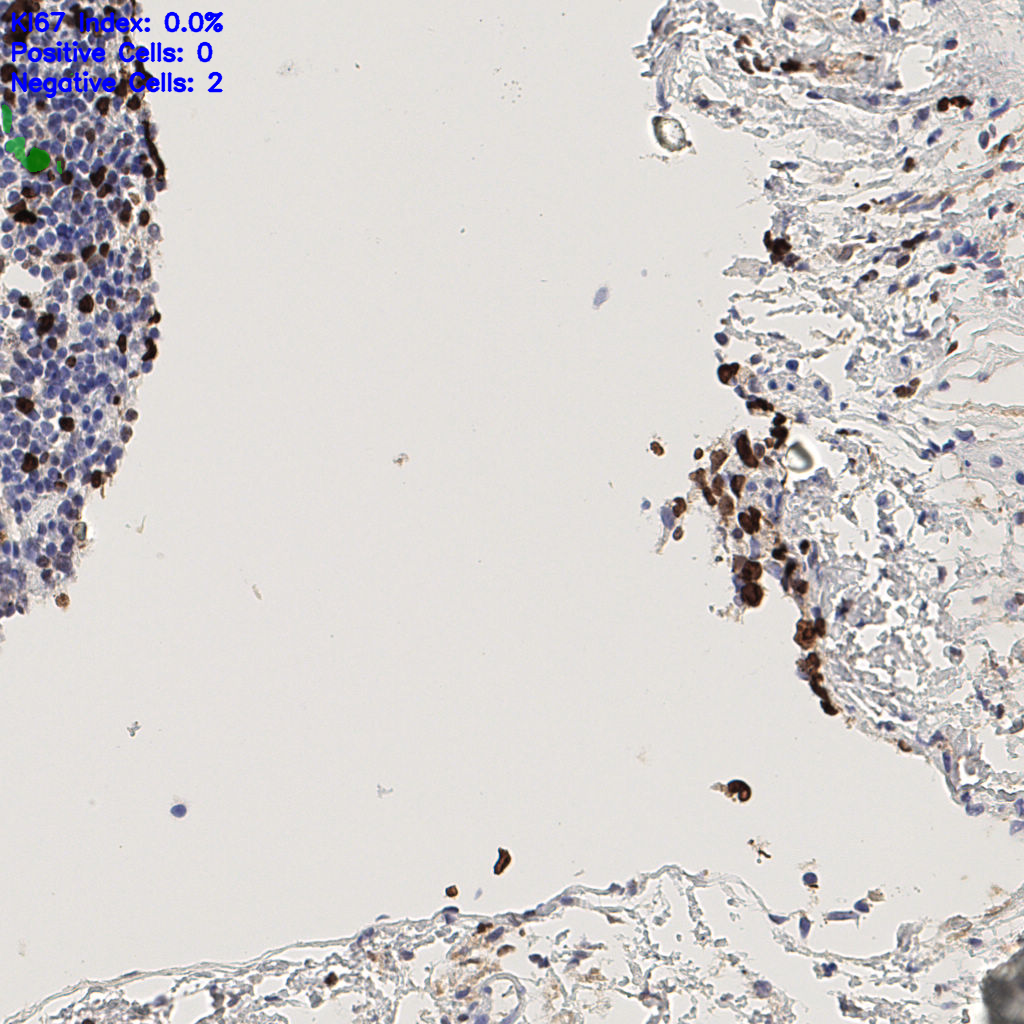

7.85%

Ki67 指数

阴 1104 阳 94

H255858-KI-67.ndpi

slice_44_5_x39424_y4480.png

slice_44_5_x39424...